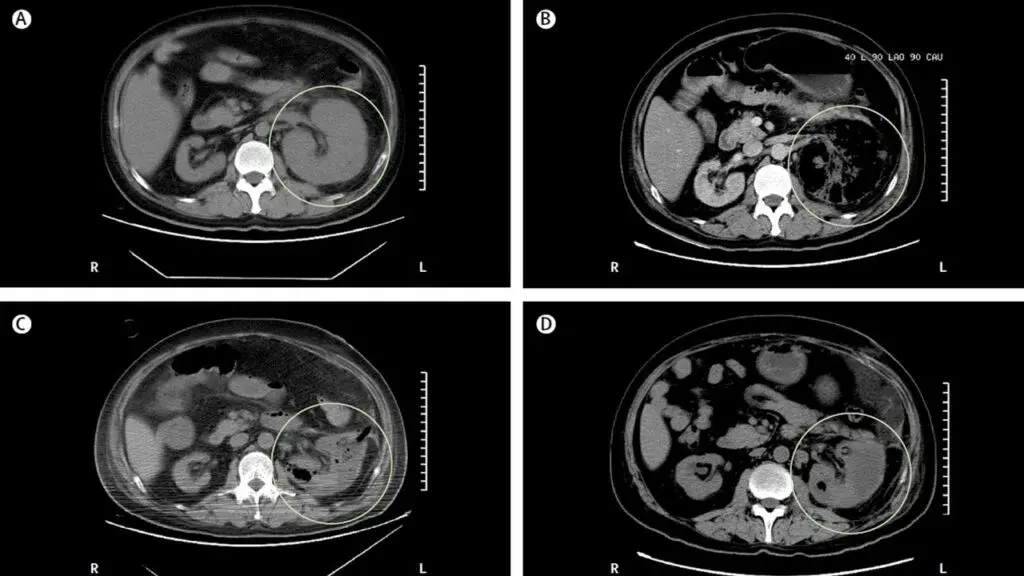

Caso típico de **pielonefritis enfisematosa** publicado en The Lancet ([link](https://www.thelancet.com/journals/lancet/article/PIIS0140-6736(19)30771-8/fulltext)). Los casos generalmente son resultado de una infección por *Escherichia coli* en pacientes con diabetes descompensada y obstrucción del tracto urinario. La glucosa es un sustrato para la proliferación de bacterias fermentadoras (*Enterobacteriaceae*) que producen dióxido de carbono e hidrógeno. **Es importante destacar el alto riesgo de embolización**. Cuando hay obstrucción presente, es obligatorio desobstruir la vía urinaria. En casos con gas en el parénquima o espacio perirrenal, se sugiere fuertemente la drenaje percutáneo. Si el gas se limita al espacio colector (pielitis aislada), el tratamiento con antibióticos es suficiente.